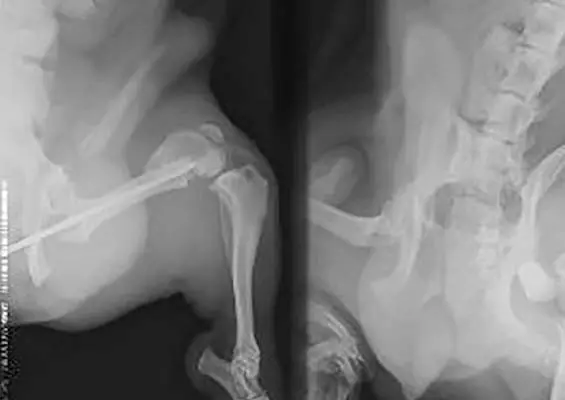

SALA OPERACYJNA

Wykorzystanie autogenicznego przeszczepu istoty gąbczastej i płyty L blokowanej w zabiegu korekcyjnym osteosyntezy kości udowej – opis przypadku